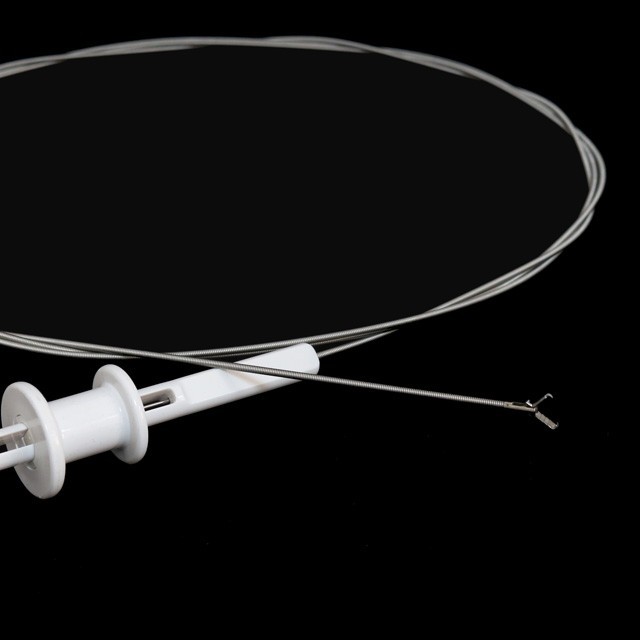

പ്രോംഗ് തരം

FG -28 U-B3 |

3- പ്രോംഗ് തരം |

FG -28 U-B4 |

4- പ്രോംഗ് തരം |

FG -28 U-B5 |

5- പ്രോംഗ് തരം |